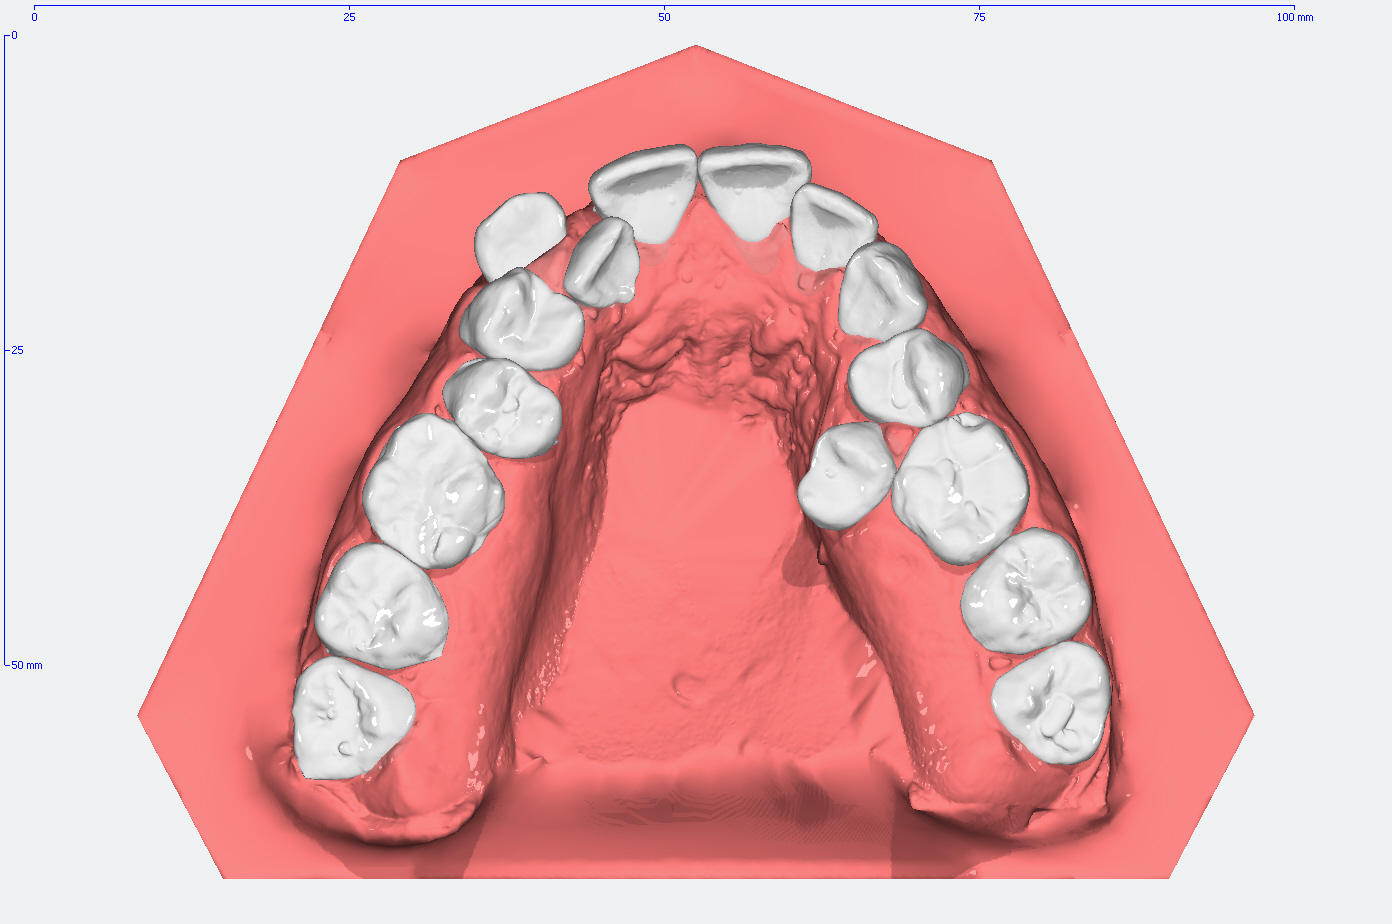

Die Entwicklung der Zahnstellung im Gebiß anhand von 3D Modellen

In den Abbildungen unten sehen Sie den Vergleich der Zahnstellung in den Gebissmodellen in der ursprünglichen Form und nach der kieferorthopädischen Behandlung.

Moderne Diagnostik mittles 3D-Modell Analyse

3D Intraoralscanner – einfacher, effektiver und angenehmer!

Anders als bei herkömmlichen Gebiss-Abformungen mit Alginat, können wir Ihre Zähne bei uns digital abformen. Dank digitalen Videotechnik scannen wir die Zähne und Ihre umliegenden Strukturen schnell, effizient und beinahe berührungsfrei.

Das System erstellt daraufhin ein dreidimensionales Abbild, das in Echtzeit auf dem Monitor betrachtet und analysiert werden kann.